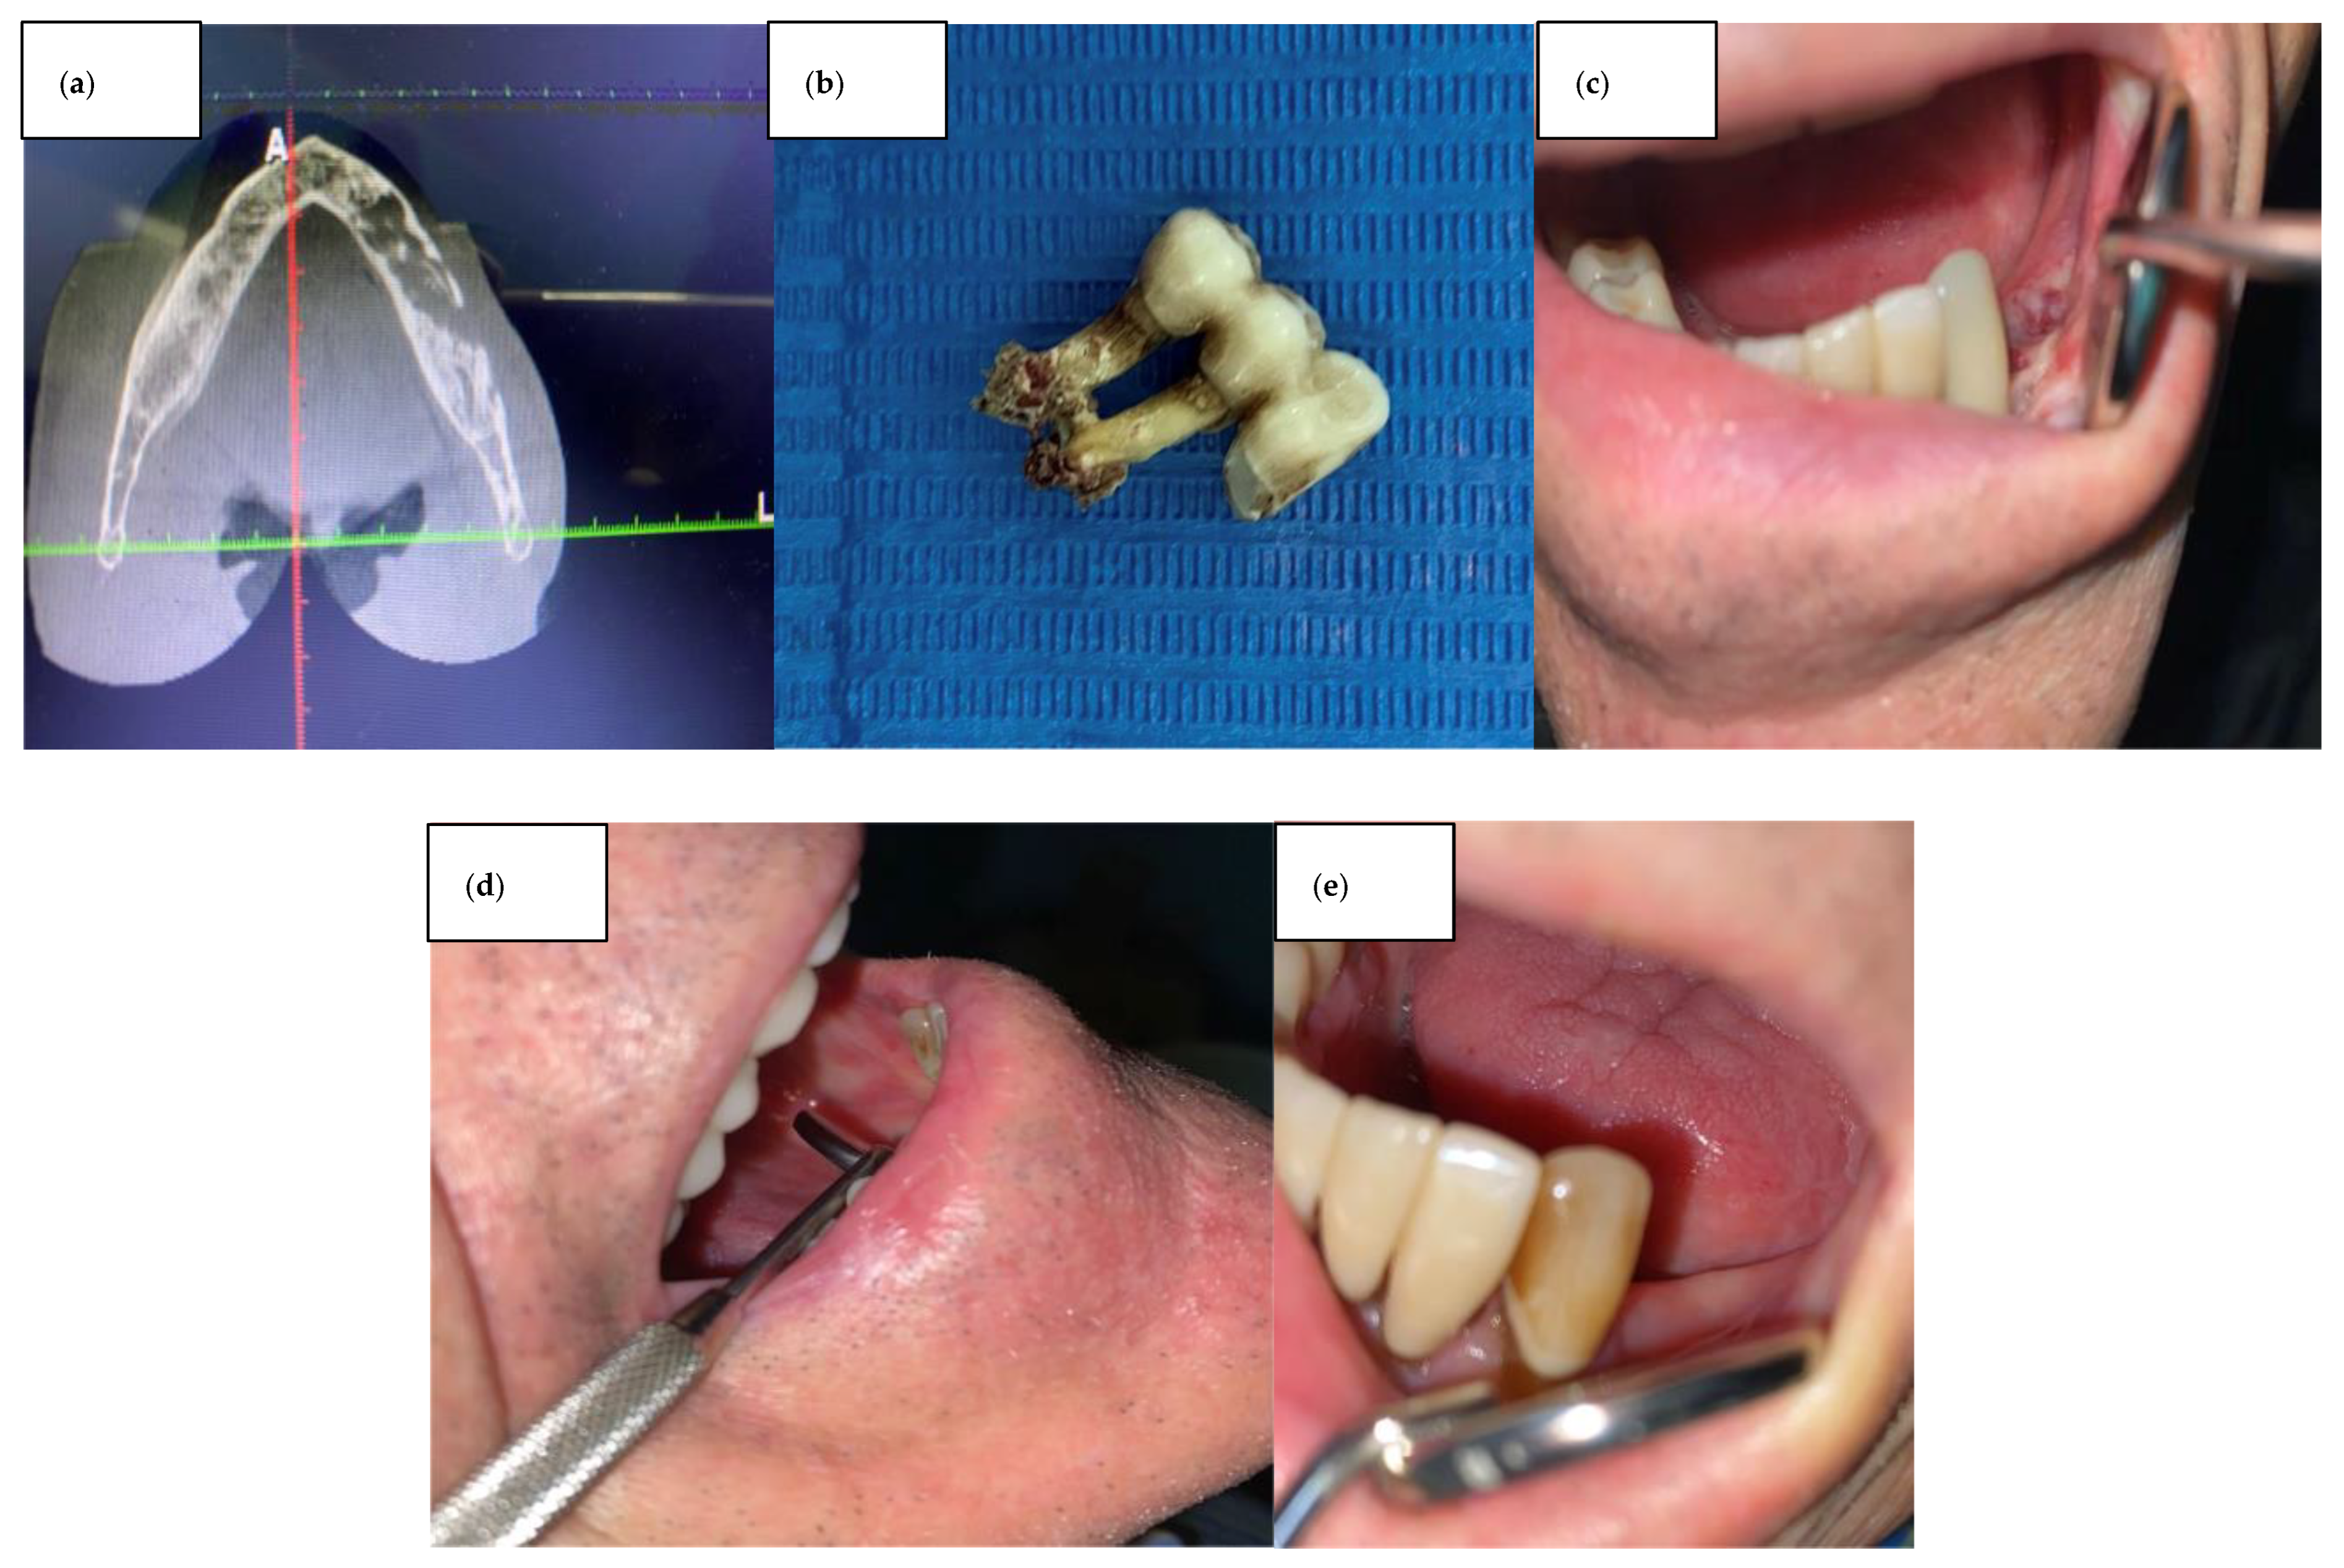

2. Case Series